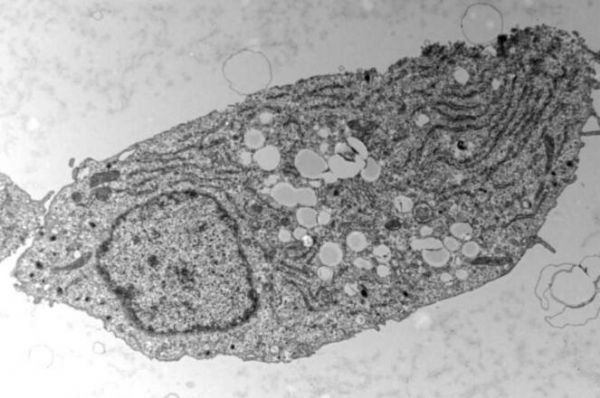

電鏡下的胰腺β細胞。

圖片來源: UNIGE - laboratoire Maechler

為了回答這個問題,研究者Pierre Maechler及其同事研究並分析了人類和小鼠機體的β細胞是如何適應過量的糖分或脂肪的。為了有效區分脂肪和糖類所產生的影響,研究人員將β細胞暴露於過量的糖和脂肪中,隨後將其暴露於在糖和脂肪的組合中;首先研究人員證實了糖類對β細胞所產生的毒性效應,即暴露於高水平糖類的β細胞所分泌的胰島素要比正常情況下少得多;當細胞同時暴露於過多糖分和過多脂肪中時,其就會以脂滴的形式來儲存脂肪,以備不時之需。讓研究人員驚訝的是,目前他們已經表明,這種儲存的脂肪並不會讓情況惡化,反而會讓胰島素的分泌恢復到近乎正常的水平,因此β細胞對特定脂肪的適應或許有助於維持機體正常的血糖水平。